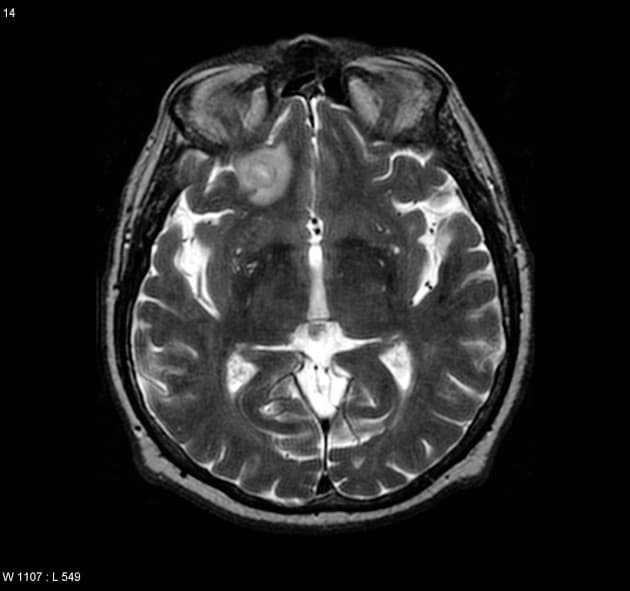

- Tổn thương dạng thùy (lobulated) kích thước 35 x 45 mm nằm ở phân đoạn V của thuỳ phải, liền kề với túi mật (gallbladder).

- Tổn thương này tăng tín hiệu (hyperintense) trên hình ảnh T2-weighted MRI.

- Trên hình ảnh cộng hưởng từ có tiêm thuốc tương phản động (dynamic contrast-enhanced imaging), thấy tăng quang dạng nốt (nodular) ở vùng ngoài viền (peripheral) ban đầu, tiếp theo là quá trình lấp đầy dần từ ngoài vào trong (slow centripetal filling).

Hình ảnh cộng hưởng từ (MRI) phù hợp điển hình với u sợi mạch gan (hepatic hemangioma).

U sợi mạch gan là khối u gan lành tính phổ biến nhất, thường được phát hiện tình cờ trên hình ảnh học. Bệnh xuất phát từ các mạch máu bất thường và gồm các khoang giãn chứa đầy máu được lót bởi tế bào nội mô. Trên cộng hưởng từ (MRI), hình ảnh điển hình bao gồm tăng tín hiệu rõ rệt trên T2 và kiểu tăng quang dạng nốt ở vùng ngoại vi trong thì động mạch, tiếp theo là quá trình lấp đầy dần từ ngoài vào trong ở các thì muộn. Dấu ấn hình ảnh này rất đặc hiệu, cho phép chẩn đoán chắc chắn không xâm lấn trong hầu hết các trường hợp. Mặc dù có thể sinh thiết, nhưng thủ thuật này tiềm ẩn nguy cơ chảy máu và thường được tránh. Điều trị mang tính bảo tồn, không cần cắt bỏ hay theo dõi định kỳ trong các trường hợp điển hình, trừ khi có nghi ngờ chẩn đoán hoặc bệnh nhân có triệu chứng.